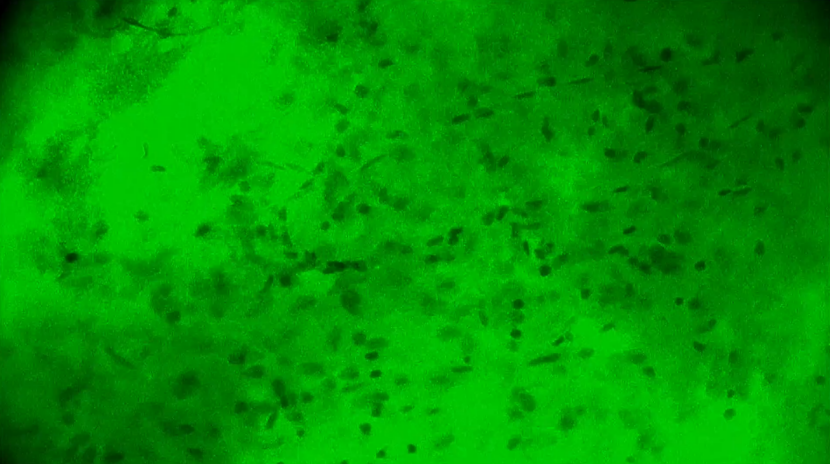

術(shù)中EndoSCell?細(xì)胞圖像如下:

第2次掃查瘤腔,一處組織的細(xì)胞核異型性明顯,分布不規(guī)則,密度較高,陽性。